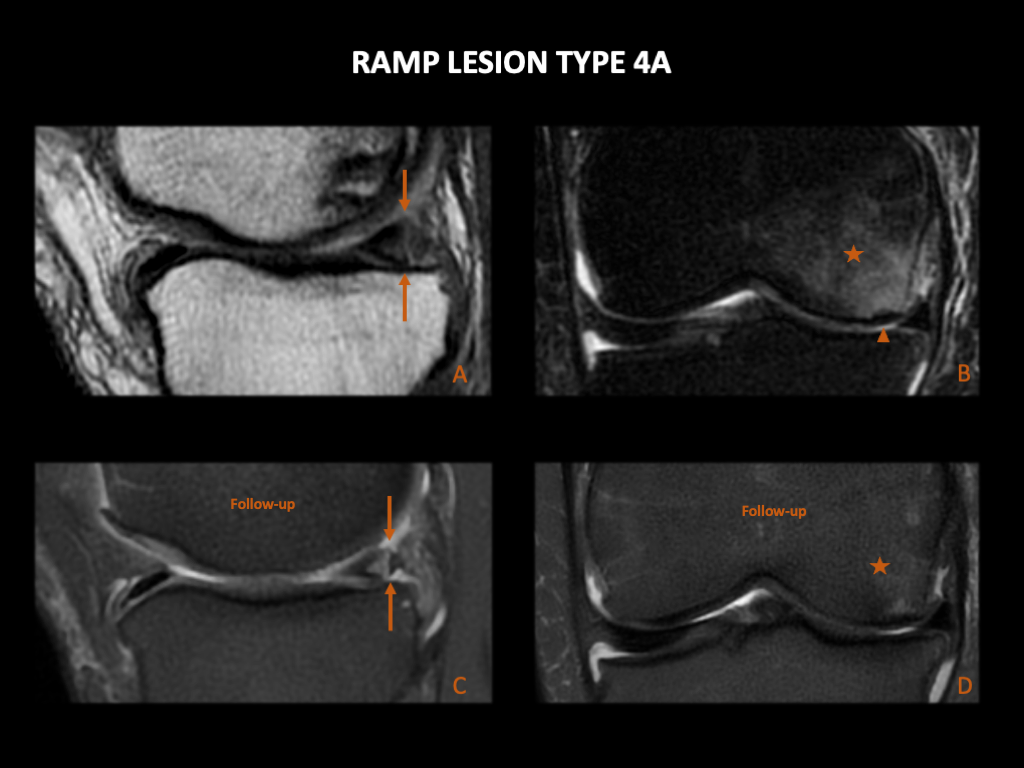

图 18:44岁,男性,左膝疼痛,出现Ramp损伤类型4A和半月板根部撕裂。左膝3T MRI (A) 矢状位PD FS,(B) 矢状位PD FS 和 (C) 冠状位T2WI FS。内侧半月板后角的“红区”有一条线性高T2信号(箭),达到上部和前部关节表面。这与Thaunat和Greif类型4A的半月板Ramp损伤一致。在图像B中,我们看到一个伴随的ACL撕裂(箭头)。在图像C中,可见内侧半月板后根部的高T2信号,与根部撕裂一致(双箭头)。(D):左膝关节镜,后内侧入路。内侧半月板的后根部已撕脱(星号)。

图 19:16岁,男性,左膝关节疼痛和不稳定,出现Ramp损伤类型4A。左膝1.5T MRI (A), (B) & (C):(A) 矢状位PD,(B) 矢状位GRE 和 (C) 矢状位T2。内侧半月板后角的“红区”有一条线性高T2信号(箭),达到上部和前部关节表面。半月板关节囊和半月板胫骨韧带完好(箭头)。这与Thaunat类型4和Greif类型4A的半月板Ramp损伤一致。在图像C中,观察到伴随的ACL撕裂(星号)。(D):术后1年的3T MRI,矢状位PD FS,(半月板缝合)。半月板呈波浪形,一些作者将其描述为半月板撕裂的间接征象,但在最初Ramp损伤发生的位置没有新撕裂的直接征象。

图 20:一名66岁女性,膝内侧区域疼痛,出现Ramp损伤类型4A。上排:右膝1.5T MRI。(A) 矢状位PD 和 (B) 冠状位T2wi FS。内侧半月板后角的“红区”有一条线性高T2信号(箭),达到上部和前部关节表面。半月板关节囊和半月板胫骨韧带完好。这与Thaunat类型4和Greif类型4A的半月板Ramp损伤一致。还有内侧股骨髁的软骨和骨皮质缺损(箭头),以及相邻骨髓的高T2信号(星号),与伴随的骨软骨损伤和骨髓水肿一致。下排:3个月后随访3T MRI。(C) 矢状位PD FS 和 (D) 冠状位T2wi FS。Ramp损伤仍然存在(箭头)。由于更高的磁场强度,半月板关节囊和半月板胫骨韧带的连续性更容易被识别。骨髓水肿几乎消退(星号)。